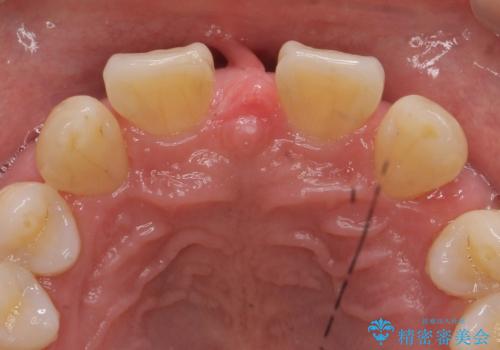

- 前歯部のすきっぱと歯並びが気になるので診て欲しいといらっしゃった方の症例です。

全顎矯正は御希望されなかったため、上顎前歯部のみの部分矯正とオールセラミッククラウンによる補綴を行いました。

今回用いたオールセラミッククラウンはジルコニアフレームという白い素材の上にセラミックを盛っているため、審美性が非常に高いのが特徴です。

また、ジルコニアは人工ダイヤモンドの材料にも使われているほど高い強度を持っており、そのためオールセラミッククラウンは審美性だけでなく、奥歯やブリッジの補綴も可能とするクラウンです。